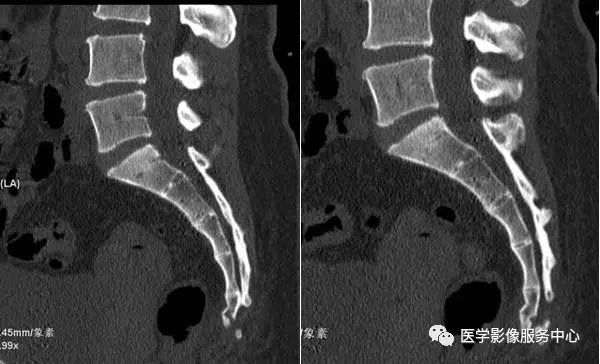

按不同的弯曲形态将其分为:均匀弯曲型、骶骨成角型、尾骨成角型、尾骨脱位型4种类型(见图1-9),其中骶骨成角一般在S3、S4-5和S5部位,成角最大为70°。尾骨成角常在尾1-2或尾2-3部位,成角最大可达80°。

图1:均匀弯曲型;图2:骶骨成角型(骶3);图3:骶骨成角型(骶4-5);图4:骶骨成角型(骶5);图5:尾骨成角型(尾1);图6:尾骨成角型(尾1-2);图7:尾骨成角型(尾2-3);图8:尾骨脱位型;图9:尾骨脱位型